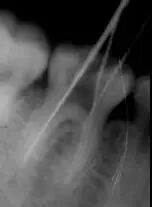

1、 开髓 洞型是否制备的符合要求,髓室顶是否揭得刚刚好,没有破坏洞壁及洞底结构。 图1、裂钻钻到近髓 图2、球钻穿髓 图3、小号锉探查根管口 图4、球钻揭髓顶 图5、修整洞型 图6、完成开髓 2、 去腐 根管预备之前是否将窝洞的腐质完全去除,避免在根管预备过程中将冠部污染带进根管; 3、 根管口的直线通道 特别对于弯曲根管!预备根管之前是否重视这个环节,尽管找到了根管口,锉也能顺利进入根管,但根管口的直线通道是否建立也是衡量医生操作技能的重要依据。方法很多:手动器械操作时我们可以采用价格便宜的“GG”钻,PROTAPER 机动预备时可以采用 SX 锉。 1、弯曲根管冠部处理之前; 2、用GG钻或SX锉进行预备; 3、处理后形成的直线通道 我的病例1_____冠部处理成直线通道后的充填效果 我的病例2_____下颌7"C"型根管的充填效果 4、 疏通中下段根管 要用小号锉 08和10号 K锉进行探查,手法是用顺反30度来回搓动的方法进入,建立根管中下段的预备通道,然后换用15号 K锉进行疏通,便于大号不锈钢器械或镍钛器械的进入。 5、 确定工作长度 15号 K锉进入时最好配合根测仪;术前,术中,术后都要拍X—RAY。 6、 冲洗方法 每次换锉之前及都要进行,但是否有效往往是不确定的,因为冲洗的效果和多方面因素有关——小号的针头(如果没有专用的针头可以用皮试的小针头),“双次冲洗法(自命名)”——即每次冲洗完毕后再用小号锉(如10号或15号)进入根管下段捣动一番,让碎屑随着冲洗液浮出根管中上段,然后进行二次冲洗,这样就能将根管内的碎屑清除彻底!注意头次冲洗后不要清除根管内的冲洗液,它的存在有非常重要的作用! 7、 建立根充档 根尖部牙本质和牙骨质的交界处不要破坏,这对后期的根充以及主尖的选择很有意义,前提是每次预备都要明确的把握工作长度! 8、 弯曲根管最好采用不锈钢锉同镍钛锉配合使用 用不锈钢器械预备弯曲根管中下段,镍钛器械预备中上段! 9、 "冠根方向”预备是可取的方法,但有些时候还是需要结合“逐步后退法"使用的。 10、 熟悉使用器械的性能及各类操作方法的临床要点 逐步后退法预备存在的一些问题——A,根管锉与根管壁接触面积大(锉进入时困难;容易被卡住;器械容易折断;碎屑容易被推向根尖区;锉尖不好控制。);B,根管成形受限(根尖区冲洗困难;碎屑清除困难;碎屑容易推出根尖孔以外引起根尖症状。)C,需要频繁换锉(操作繁琐;临床操作时间长。)因此,很多牙医已经不采用该法,取而代之使用的是采用镍钛器械进行冠根向预备法“Crown Down”。但不锈钢器械(如K锉)还是有它的用途——小号K锉可以用来寻找根管以及进行根管疏通;用来确定工作长度;用来进行根尖预备;弯曲根管配合镍钛器械进行预备比较安全! 问题答案:这个病例的问题主要反应在开髓的洞形修整,注意观察该牙X-RAY的左侧洞壁,如果常规情况制备成这样是由于裂钻破坏了洞壁和洞底所形成的台阶。如果评估根管治疗的质量那是要扣分的!但这个病例仔细观察洞壁形态就可以看出:该病例属于再治疗的病例,因此还是属于一个理想的病例。 图文来源网络,版权属于原作者 转载只为分享,如有侵权,请联系删除 扫一扫 | 客服微信 了解更多 | 行业招聘资讯 - 医招职达 - 让人才更有价值 做精准高效的口腔人力资源服务平台